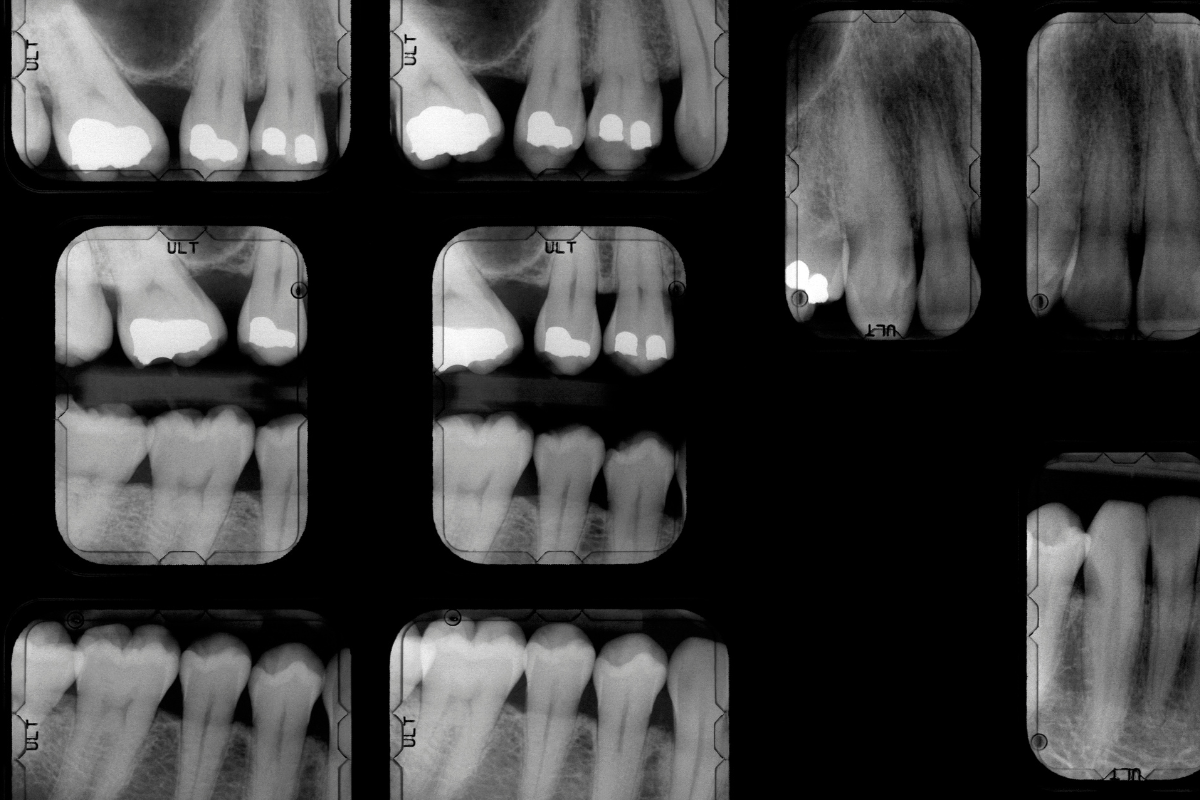

Doplňková diagnostika

Testy vitality zubů, sondáž parodontu, fotografická dokumentace, intraorální kamera a další individuální metody dle potřeby.